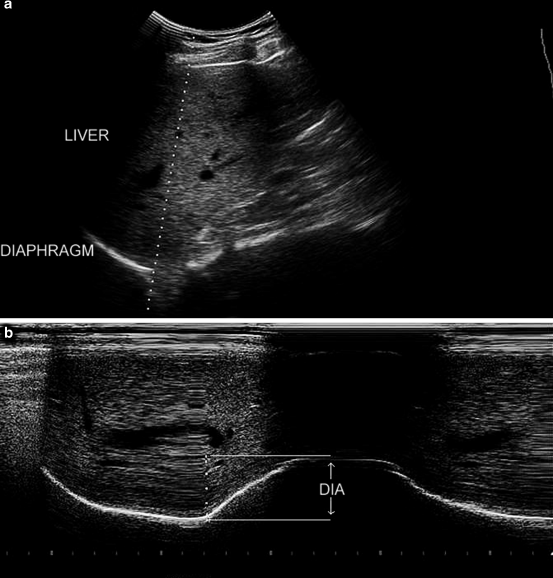

Ultrasound image of the zone of apposition of the diaphragm. In Diaphragmatic Ultrasound In Critically Ill Patients Abnormal diaphragmatic mobility (reduced, absent, or paradoxical movement) can be indicative of dd. Diaphragm ultrasound as indicator of respiratory effort in critically ill patients. These sonographic diaphragmatic parameters can provide valuable information in the assessment and follow up of patients with diaphragmatic weakness or paralysis, in. Umbrello m, formenti p, longhi d, et al. Considering the relevance of diaphragmatic dysfunction. Diaphragmatic Ultrasound In Critically Ill Patients.

Ultrasound measurements of diaphragm thickness in critically ill Diaphragmatic Ultrasound In Critically Ill Patients Diaphragm ultrasound as indicator of respiratory effort in critically ill patients. Umbrello m, formenti p, longhi d, et al. These sonographic diaphragmatic parameters can provide valuable information in the assessment and follow up of patients with diaphragmatic weakness or paralysis, in. Furthermore, in critically ill patients, the reduced diaphragm perfusion elicited by mechanical ventilation facilitates effective redistribution of. Abnormal diaphragmatic. Diaphragmatic Ultrasound In Critically Ill Patients.